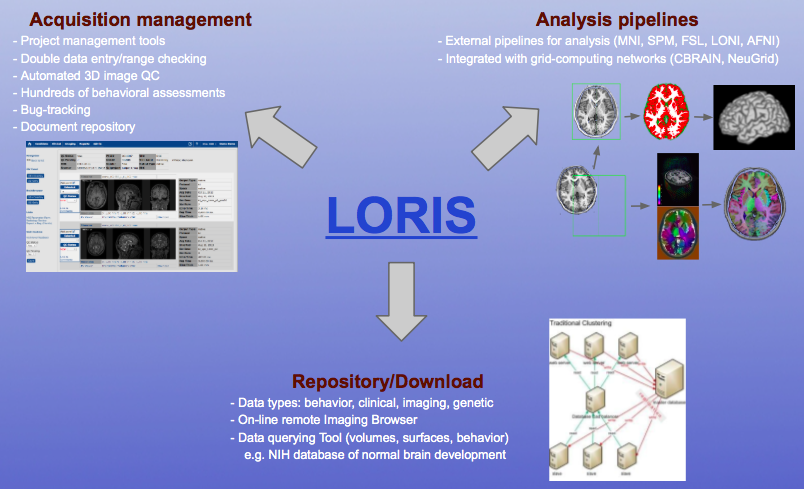

What does LORIS do?

What does LORIS do?

What does LORIS actually do?

1. Acquisition & Storage

What can LORIS do (pointform)

- Long Term Storage - Large datasets are valuable assets (e.g. ADNI)

- Anonymity/Privacy - Ethics/IRB compliance and patient confidentiality

- Data Sharing - Cross project collaborations

- Secure Web Access- Available through a web browser

- Heterogeneous Data Management - Single platform for MRI, PET, Clinical & Genetics data

- Multimodal Data Querying - Easy querying of data, without requiring a programmer

- Quality Control - Protocol violations, artefact detector, inter-rater reliability

- Summary Statistics - Demographics, imaging, data entry

- Processing Platform - Seamless serving of data to processing environments

- Radiological Reviews - Visualization, including module to curate

- Import/Export Capabilities - .xls, .csv, etc.

- Biobanking - Tissue, blood and saliva samples

- Visualization - 3D and 4D

- Customizable & Extensible - New modules and features are possible

- Open Source - Full access to source code. Code is free.